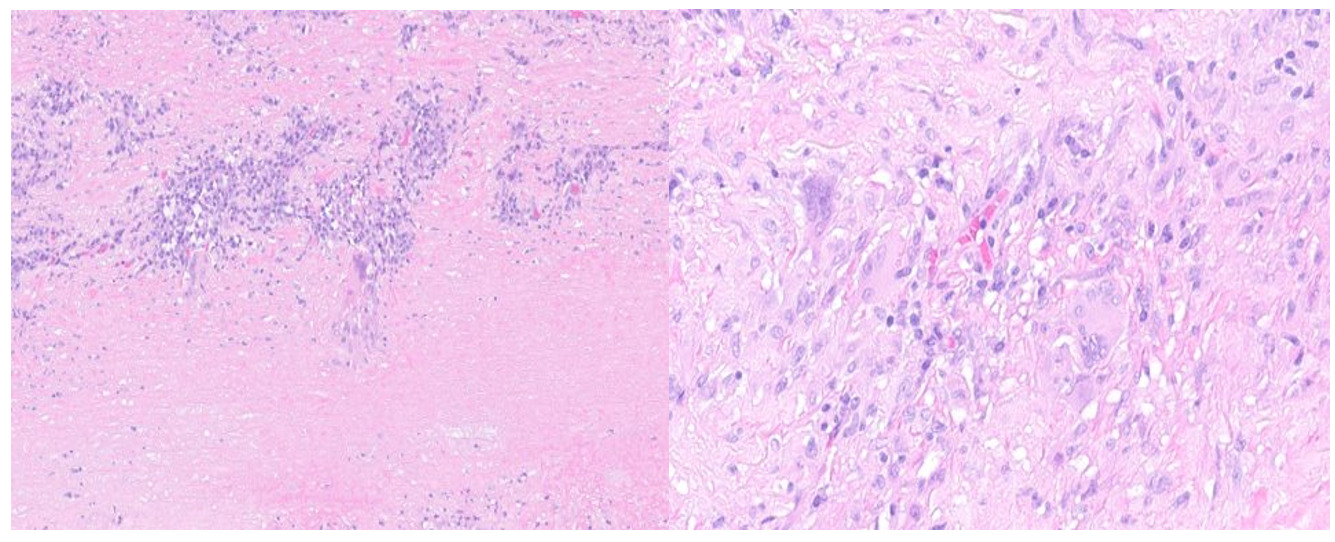

Aortic root pathology showed significant destruction of aortic wall with extensive necrosis and fibrosis (Figure 4).

Higher magnification revealed transmural lymphoplasmacytic inflammation and scattered multinucleated giant cells (Figure 5).